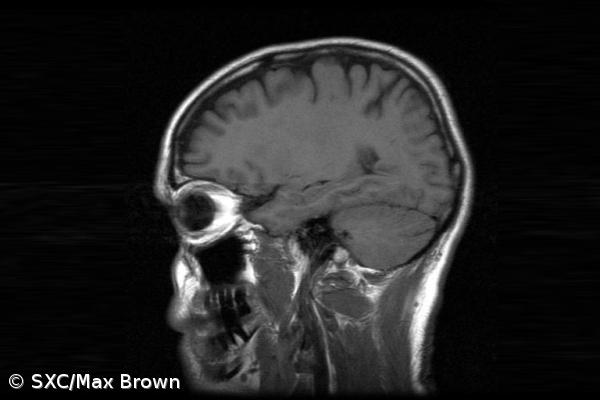

A maioria dos animais tem corpos com simetria espelhada (esquerda e direita são iguais, mas invertidas), propriedade que o cérebro partilha, exceto no caso de algumas funções cognitivas que parecem lateralizadas.

Até ao momento, os mecanismos biológicos que fazem com que essa simetria no cérebro desapareça, em alguns casos, não são bem compreendidos.

O investigador do Conselho Superior de Investigação Científica (CSIC), em Espanha, Luis Seoane, desenvolveu uma nova teoria matemática que demonstra como o aparecimento de mais complexidade cognitiva acarreta uma pressão evolutiva que favorece a lateralização cerebral.